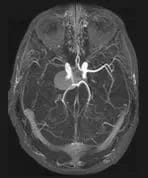

Right Internal Carotid Artery Aneurysm

A patient presents with longstanding headaches.

Findings

A contrast enhanced 3DTOF MRA with post processing reformatted images demonstrates a large right supraclinoid aneurysm. The entering and exiting vessels lie at the anterior aspect of the aneurysm.